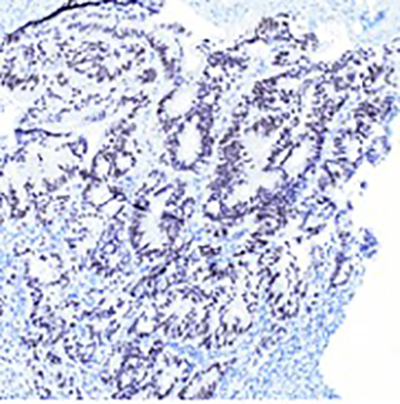

Fig. 1 Adenocarcinoma embedded in endometrial stroma (A and B). Adenocarcinoma with dirty necrosis (C) and intracytoplasmic mucin (D). The malignant cells are negative for CK-7 (E) and positive for CK-20 (F), CDX-2 (G), SATB-2 (H).

B. 400X